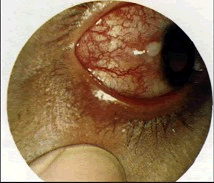

(如图)该种疾病的病因可能是由于()

-

(如图)该疾病的说法正确的是()